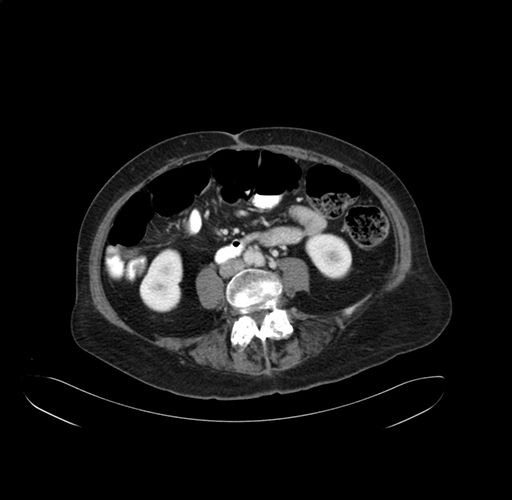

Axial Venous